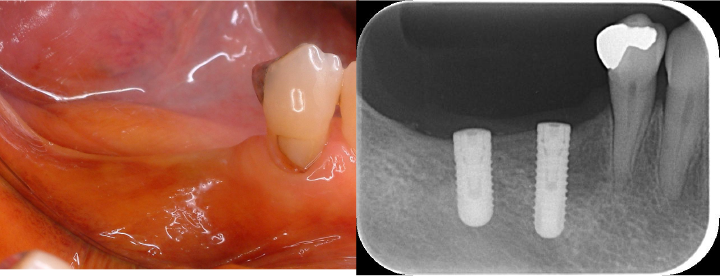

初診時口腔内写真5枚法

初診時口腔内写真五枚法です。

主訴である右上2~左上1は初診日に仮歯に置き換えてあります。

デンタル10枚法及びプロービングチャート

デンタル10枚法及びプロービングチャートです。

全体的には歯槽骨の吸収はみられませんが、左下7は左下8の影響により、遠心部に垂直性の骨欠損がみられます。

右上2から左上1には不十分な根管充填がみられます。

他院にて右上前歯が虫歯で抜歯と診断

他院にて右上の前歯は虫歯と根の先にできた炎症で保存ができないと言われて当院を受診されました。

強く保存を希望されたため、根管治療と矯正治療、歯周形成外科を行い保存を試みることにしました。

根管治療終了時口腔内写真およびレントゲン写真

根管治療終了時のレントゲン写真及び口腔内写真です。右上1番の根尖病巣の縮小がみられるため、保存可能と判断し矯正治療を行うことにしました。